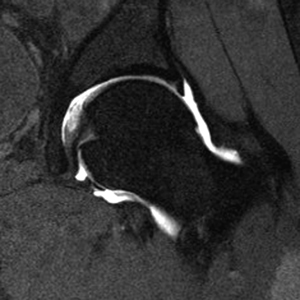

An MRI arthrogram exam is an imaging study. It is used to take detailed pictures of your joints. MRI stands for magnetic resonance imaging. This exam has 2 parts. First you will have an arthrogram and then an MRI. This 2-part exam shows more details of your joint than an MRI by itself. It will help your healthcare provider decide which treatment is best for your medical condition.

- Joints such as knee, hip, and shoulder are made up of 2 bones that fit closely together. Other tissues (cartilage, tendons, and ligaments) support and cushion your joints. An MRI arthrogram helps your doctor see small tears or other problems in these tissues. The results of this exam will help guide your treatment. It will also help your doctor keep track of problems in your joint.

Part 2: The MRI

- You will lie on a sliding table. The MRI technologist will help you get into position for the exam.

- A device called a surface coil will be placed around the joint that is being examined.